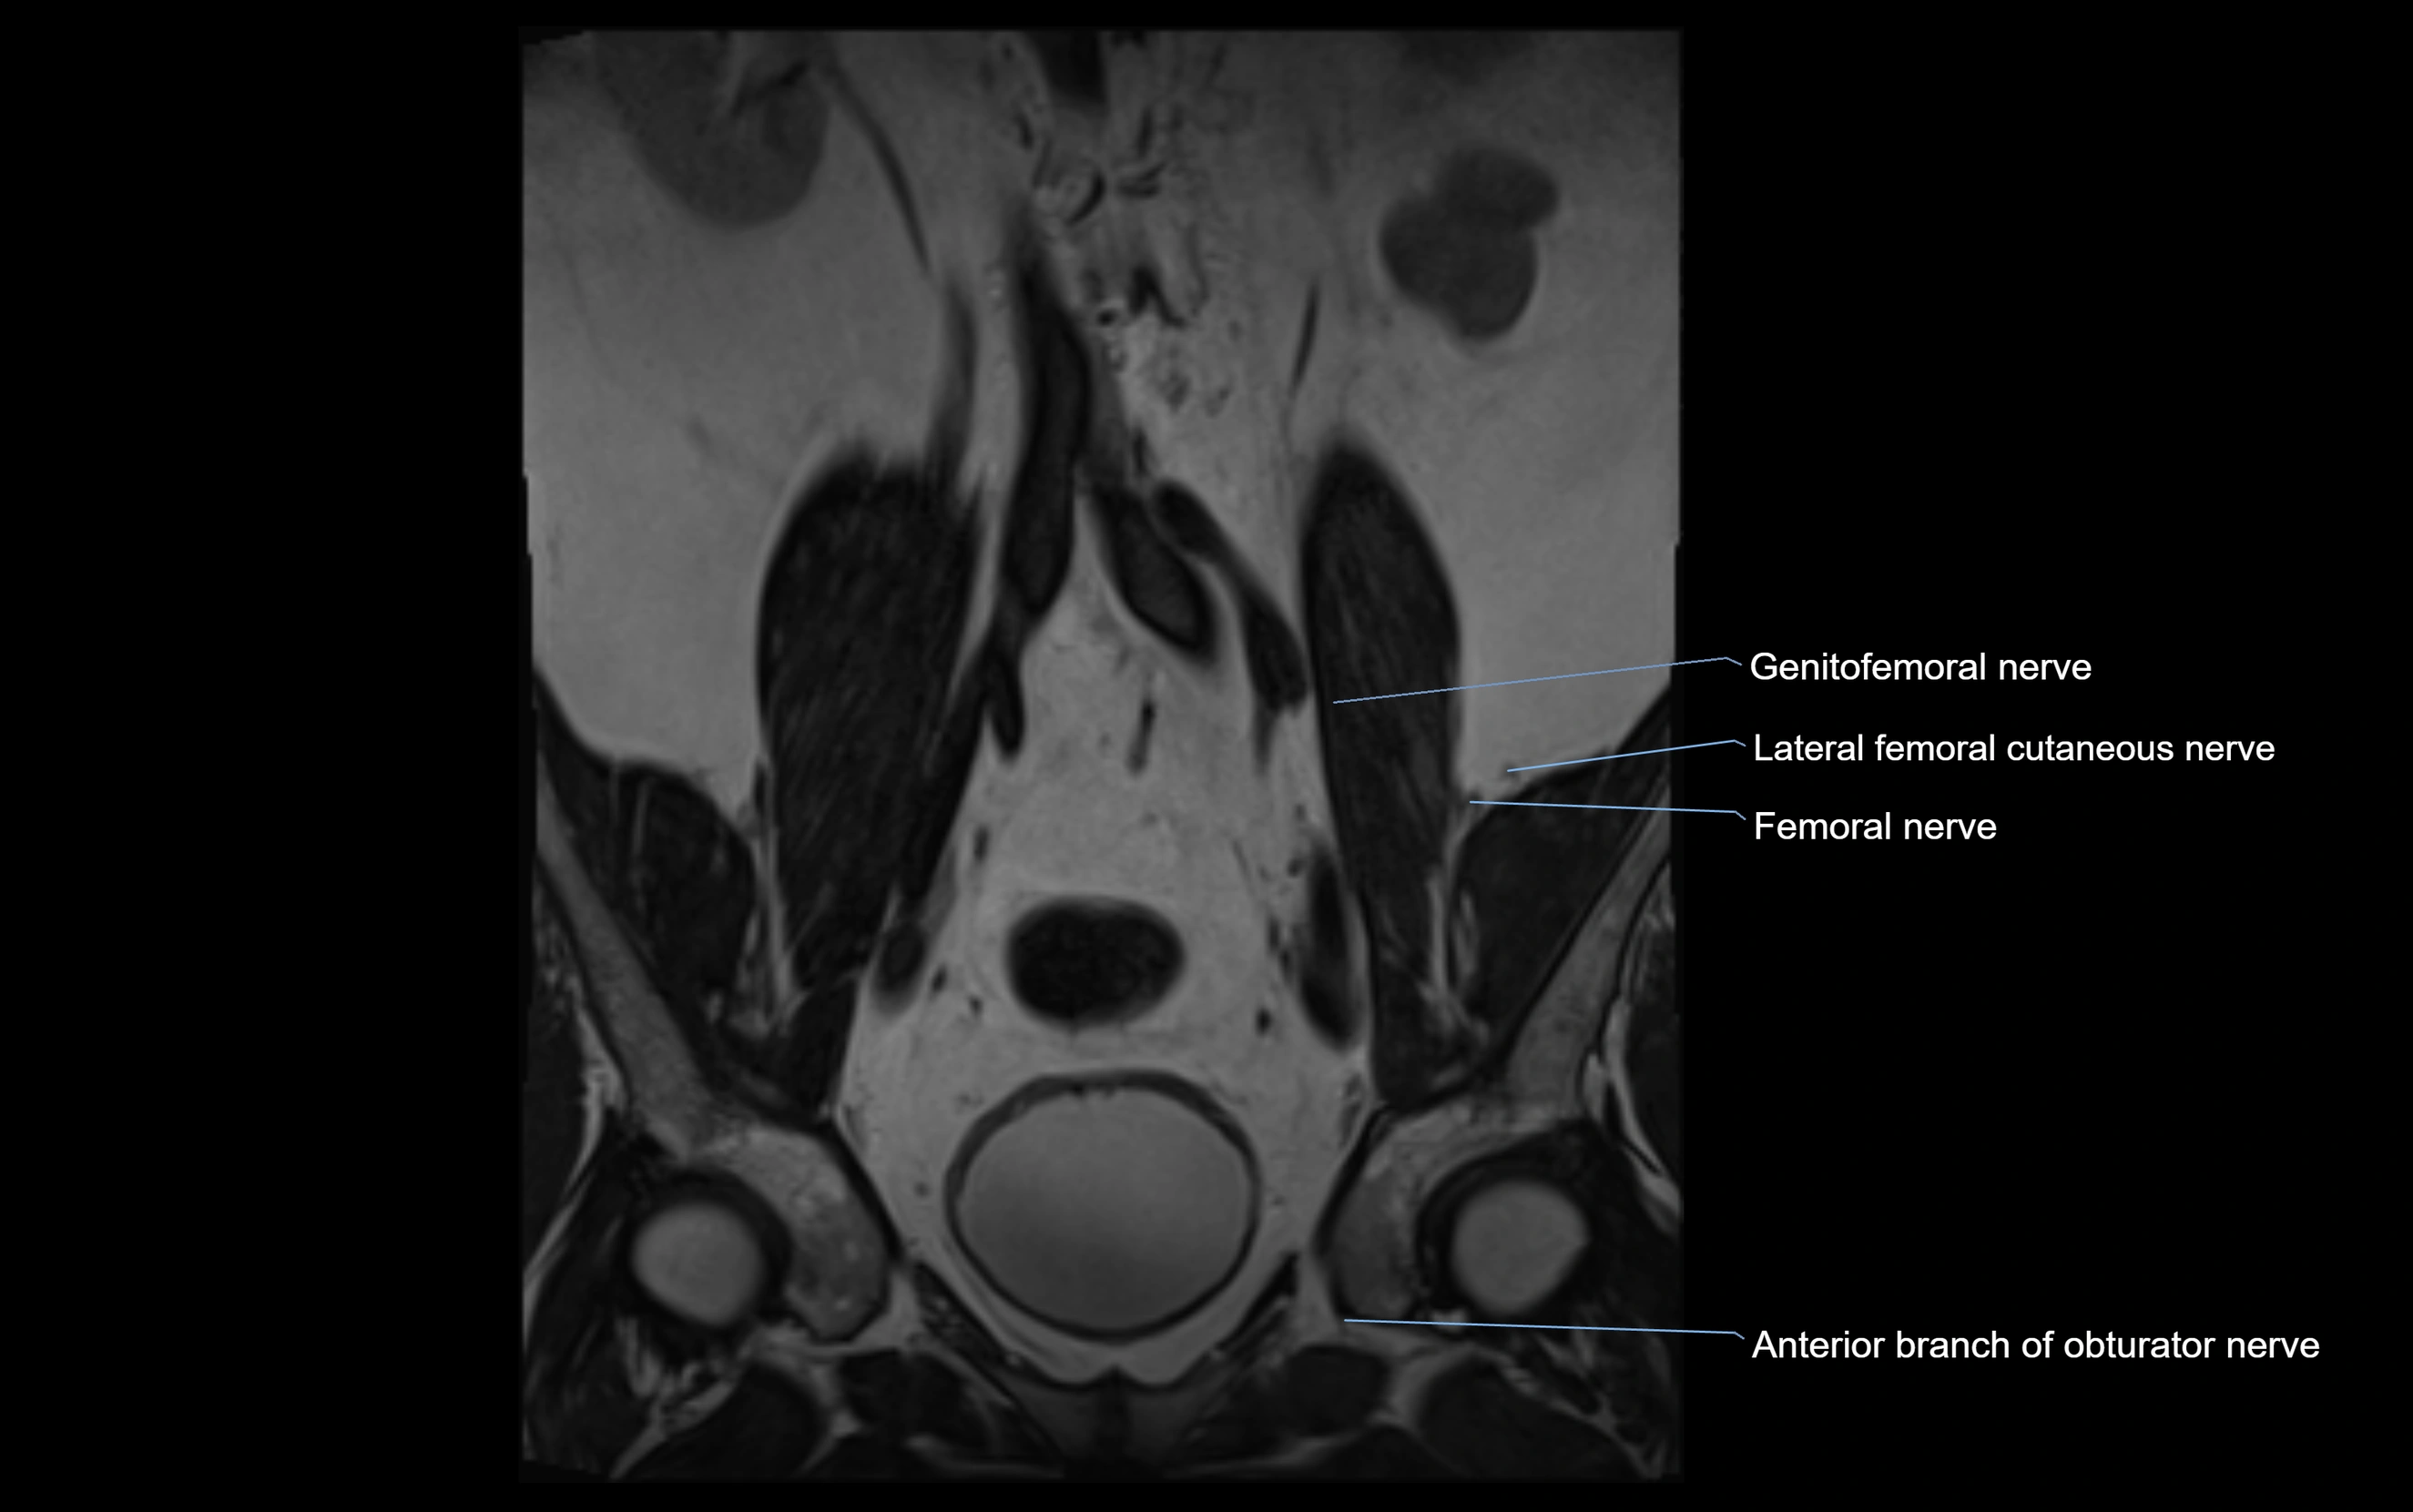

MRI image

image